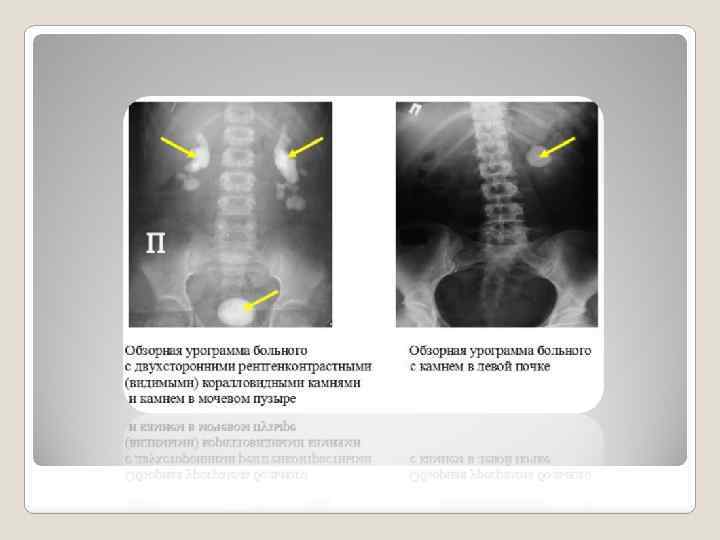

Обзорная рентгенография показана с целью обнаружения и локализации рентгенопозитивных (рентгеноконтрастных) теней, подозрительных на конкременты, в проекции почек, мочеточников и мочевого пузыря. Камни могут быть рентгенопозитивными (рентгеноконтрастными), рентгенонегативными (рентгенонеконтрастными) или малоконтрастными, что зависит от химического состава (прежде всего, присутствия и количества кальциевого компонента) мочевых камней. Конкременты, состоящие из кальцийоксалатов и кальций-фосфатов, отчетливо видны на рентгенограммах. Камни, состоящие из мочевой кислоты и ее солей (ураты), на обзорных рентгенограммах не видны. «Невидимость» камня на обзорном снимке может быть обусловлена не только химическим составом, но и плохим качеством снимка, проекцией камня на кости скелета и прочими причинами (асцит, ожирение и т. д. ). Камни почки и мочеточника нередко приходится дифференцировать от обызвествленных лимфатических узлов и флеболитов в области таза, камней желчного пузыря, теней каловых масс, инородных тел кишечника. Уточнить характер и локализацию тени помогает экскреторная урография.